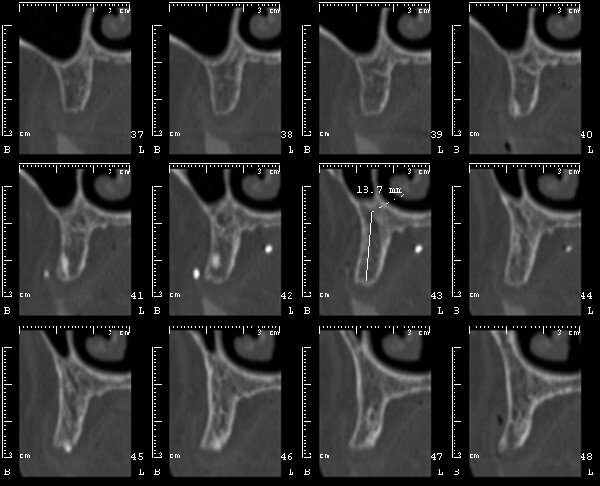

La nuova protesi totale provvisoria ha portato immediatamente un miglioramento funzionale ed estetico, con un notevole beneficio psicologico sulla paziente ed un enorme vantaggio per il prosieguo della terapia (Figg. 8-10). Il nuovo montaggio con denti di maggiori dimensioni ed una differente occlusione ha conferito un miglior supporto al labbro superiore ed una migliorata estetica del sorriso (Fig. 11). Alla luce della nuova situazione, accettata e gradita dalla paziente, si è incominciato a pianificare la procedura chirurgica. Avendo la CBCT evidenziato dei volumi ossei adeguati (Fig. 12), si è proceduto allo studio del caso mediante un software di chirurgia guidata (Simplant, Dentsply-Sirona) (Figg. 13, 14).